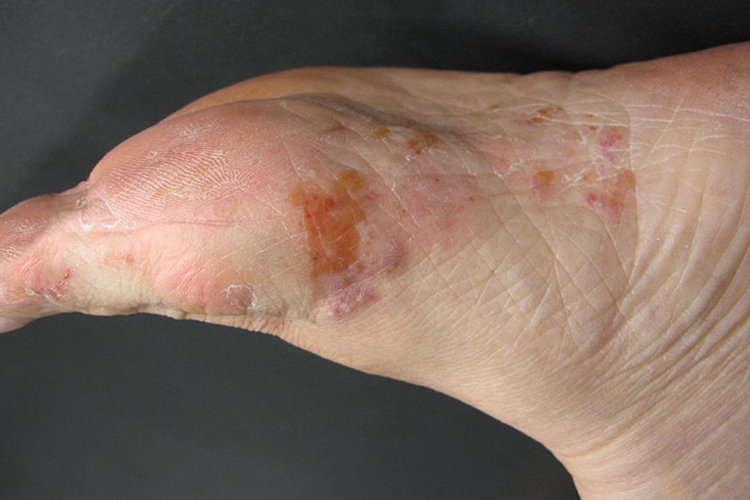

手癣和足癣相似,根据临床特点分为水疱型、鳞屑角化型、浸渍糜烂型三种。

水疱型:皮损初为针尖大小的深在水疱,疱液清,壁厚而发亮,不易破溃,可融合成多房性大疱,撕去疱壁露出蜂窝状基底及鲜红糜烂面,干燥吸收后出现脱屑,瘙痒明显。

鳞屑角化型:皮损呈弥漫性皮肤粗糙、增厚、脱屑、干燥,冬季易发生皲裂甚至出血,可伴有疼痛,一般无明显瘙痒。

浸渍糜烂型:表现为皮肤浸渍发白,表面松软易剥脱,露出潮红糜烂面及渗液,常伴有裂隙,有明显瘙痒,继发细菌感染时有臭味。